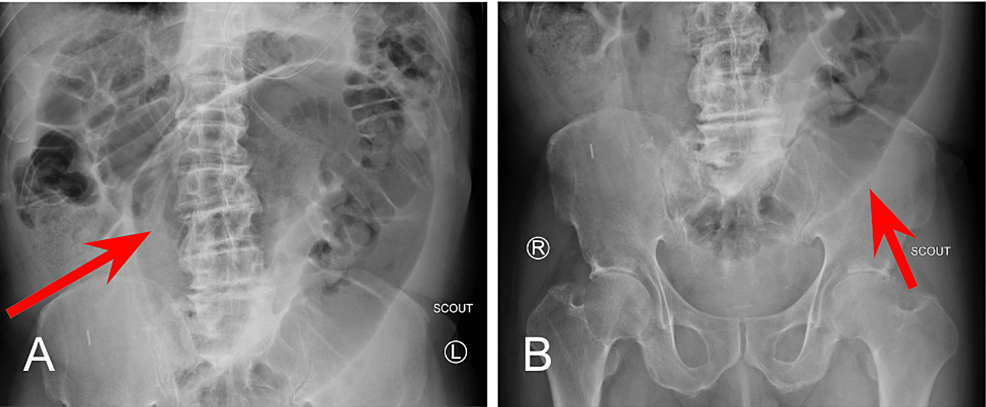

At the 1 minute mark (Figure 2A), opacification of the stomach following administration of contrast material via NG tube can be noted. At the 30-minute mark (Figure 2B), normal transit of contrast into the proximal small bowel can be visualized within the duodenum.